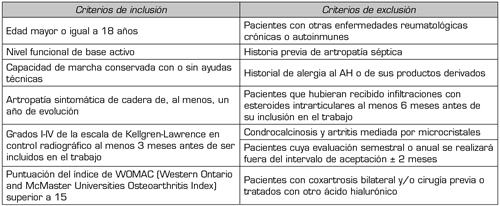

Fueron objeto del estudio aquellos pacientes referidos a nuestro servicio entre enero de 2016 y diciembre de 2020, con diagnóstico de artrosis sintomática de cadera, tratados en el Servicio de Medicina Física y Rehabilitación de nuestro centro hospitalario. Los pacientes fueron admitidos desde las consultas externas del servicio, bien en el propio centro o en los centros de atención especializada del área sanitaria correspondiente. Los criterios de inclusión y exclusión están definidos en la Tabla I.

Tabla I. Criterios de inclusión y exclusión empleados para la selección de los pacientes del estudio.